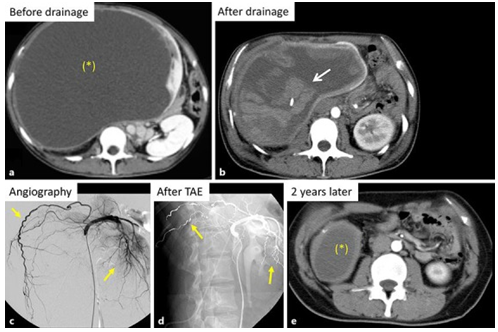

Toriu et al. [3] encountered 2 patients who had huge symptomatic simple kidney cysts With regard to the first case severe intra-cystic bleeding did occur pursuant to drainage of the kidney cyst and this was treated successfully by means of trans-arterial embolization (TAE). With regard to the second case, trans-arterial embolization (TAE) was undertaken prophylactically, and there was no bleeding associated with subsequent drainage of the kidney cyst. Toriu et al. [3] summated the cases as follows:

Case 1:

In August 2007, a 24-year-old Japanese woman was admitted into an outside hospital in order to investigate her symptoms of abdominal pain and abdominal distension. She had contrast-enhanced computed tomography (CT) scan of abdomen which demonstrated a huge homogeneous cyst that measured 50 cm x 25 cm x 18 cm that amounted to a total volume of 11,775 mL within her right kidney. The cyst was were noted to be thin and the lesion was noted to be sharply delineated from her renal parenchyma and based upon the features of the cyst, it was categorised as Bosniak Category I cyst based upon the Bosniak Classification. [1] (see figure 1a). Per-cutaneous catheter drainage of the kidney cyst was undertaken under ultrasound scan-guidance. Immediately after 4,000 mL of the cyst fluid was drained, the patient did develop severe abdominal pain and her haemoglobin dropped from 11.0 g/dL to 7.3 g/dL. In view of this further drainage and sclerotherapy of the cystic space was not undertaken. She had a CT scan of abdomen which demonstrated bleeding into the kidney cyst (see figure 1b). She did receive 800 mL of packed red blood cells. Nephrectomy was recommended; nevertheless, the patient expressed her wish to preserve her kidney and in view of this she was referred to the hospital of the authors. In her new hospital she had renal artery angiography which demonstrated elongated and narrow branches of her right renal artery encompassing the huge right renal cyst (see figure 1c). TAE was undertaken with utilization of 28 platinum micro-coils based upon the previously reported reports [4] [5] which resulted in occlusion of the feeding arteries while preserving the residual right kidney parenchyma. (see figure 1d). Pursuant to the TAE, the intra-cystic bleeding stopped and percutaneous catheter drainage was again undertaken under ultrasound scan-guidance and 4,000 mL of bloody fluid was drained. At her 2-years follow-up assessment, her right renal cyst had reduced to measurements of 6 cm x 4 cm x 4 cm with a volume of 75.4 mL (see figure 1e).